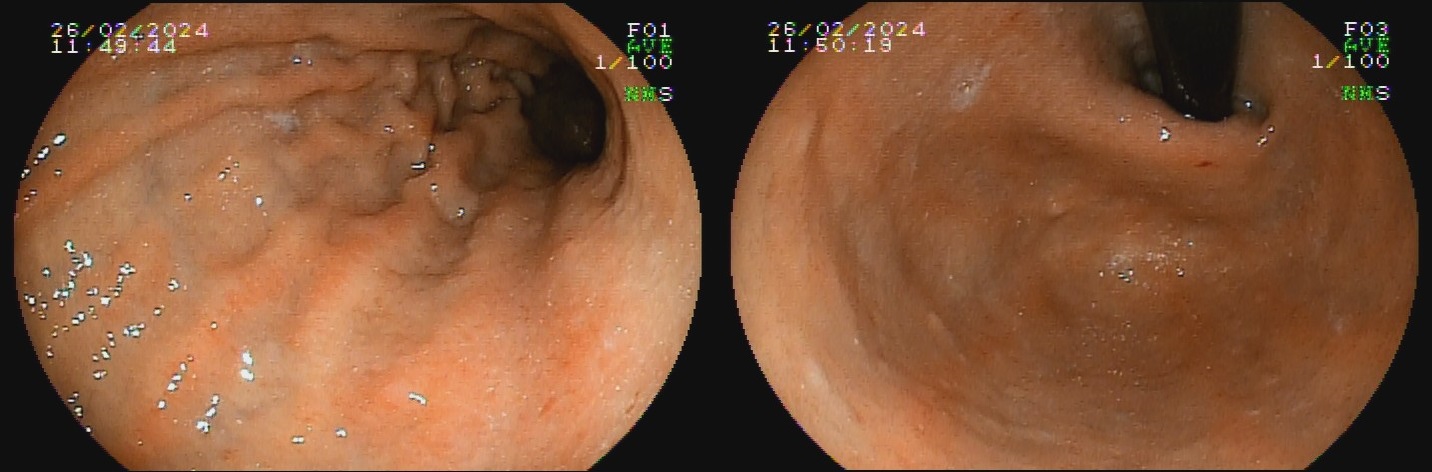

Já a gastrite atrófica autoimune ocorre por destruição glandular por autoanticorpos anticélulas parietais, e é mais comum em mulheres, porém dados relativos à idade e etnia mais frequente são controversos. A inflamação crônica resulta em redução do relevo e palidez da mucosa de fundo e corpo, assim como desaparecimento do pregueado mucoso observado à insuflação durante o exame endoscópico, com aspecto mais homogêneo que aquele encontrado na gastrite atrófica infecciosa. Podem ser formadas ilhas de mucosa normal residual, caracterizadas endoscopicamente como pseudopólipos. A mucosa do antro mantém-se preservada por não apresentar células parietais, delimitando uma área de transição clara entre a mucosa atrófica do corpo e mucosa normal do antro.